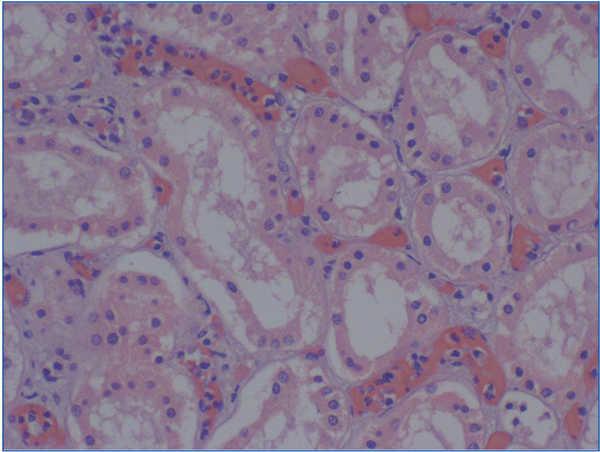

Peritubular capillary multilamination (transplant capillary disease) (Figure 6) is another of the histological findings to diagnose of chronic rejection.54,55 Its diagnosis must be very accurate48 and requires an ultrastructural study. Monga et al46,47 described the association between TG and multilamination of the basement membrane of the peritubular capillaries (PTC). Drachenburg et al57 have shown that TG is associated with a severe multilamination of PTC (more than six laminates), while less serious levels of lamination (2-3 laminates) can also be seen in other types of glomerular diseases, both in the native kidney and in the allograft.

Figure 6. Transplant capillary disease